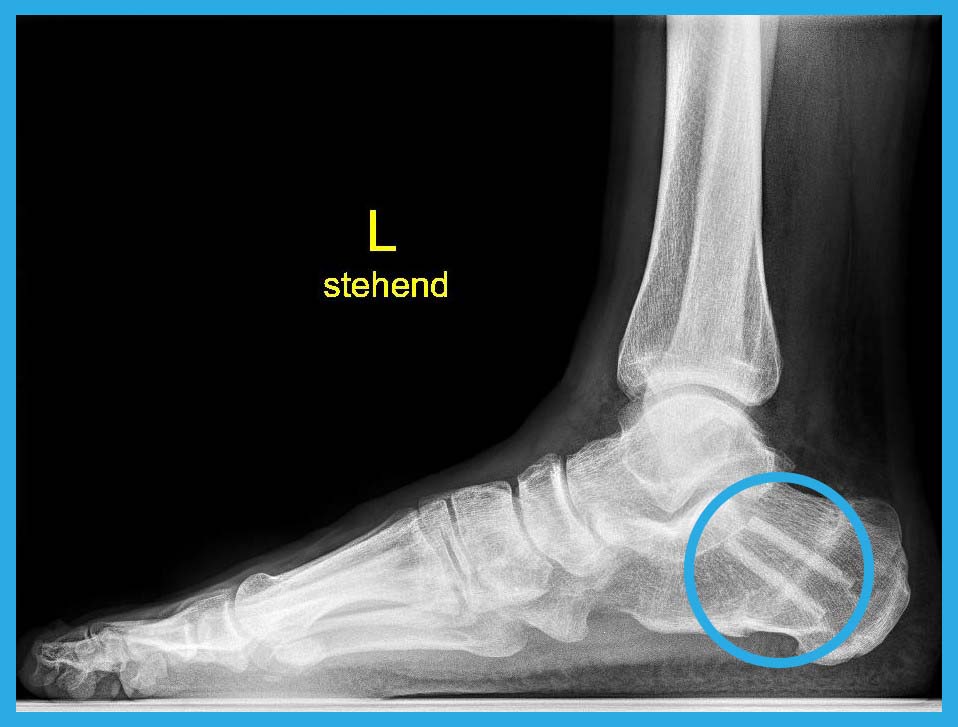

Left/Top: Illustration of flat feet before surgery.

Right/bottom: Image of flat feet after surgery with Shark Screw®.

The left/upper image shows auntreated flat feet before surgery. The right/bottom picture shows flat feet treated with Shark Screw® after surgery.